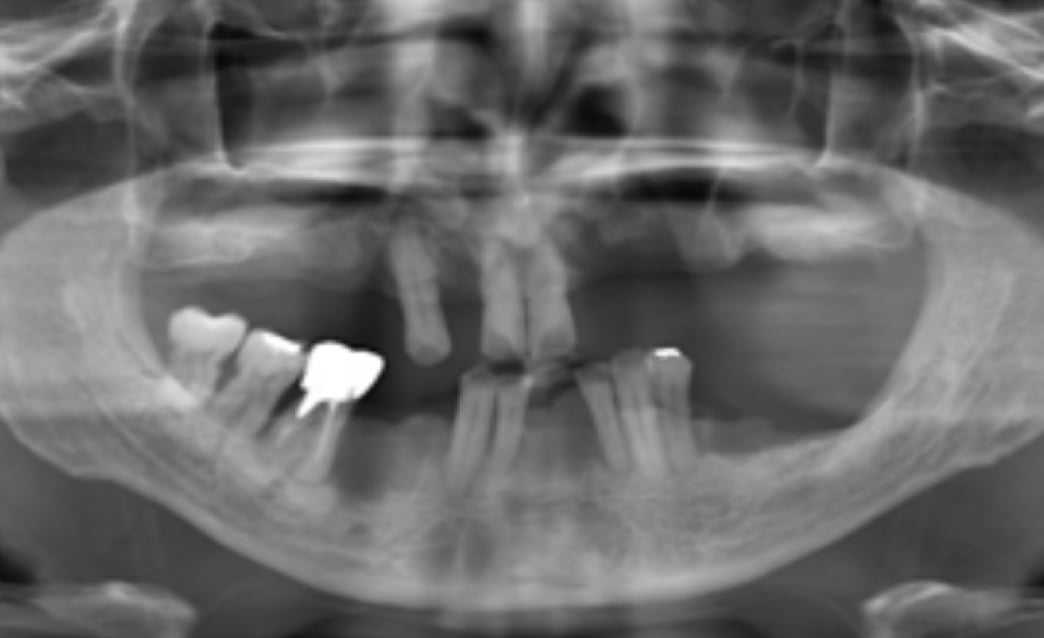

60代

Before

After

| 主訴 | 歯がぐらぐらする。 |

| 治療内容 | 下顎の残存歯は、歯周病が進行していたため全て抜歯をおこない、同日にインプラント埋入と仮歯の装着をしました。骨とインプラントが固定されるのを約3ヵ月待ち、型どりをして最終補綴を装着します。上顎にはフルデンチャーを使用し、快適に食事がとれています。 |

| 治療期間 | 6ヵ月 |

| 費用 | ¥3,586,000(税込み) |

| リスク・副作用 |

・外科処置が必要。コストがかかる。 |